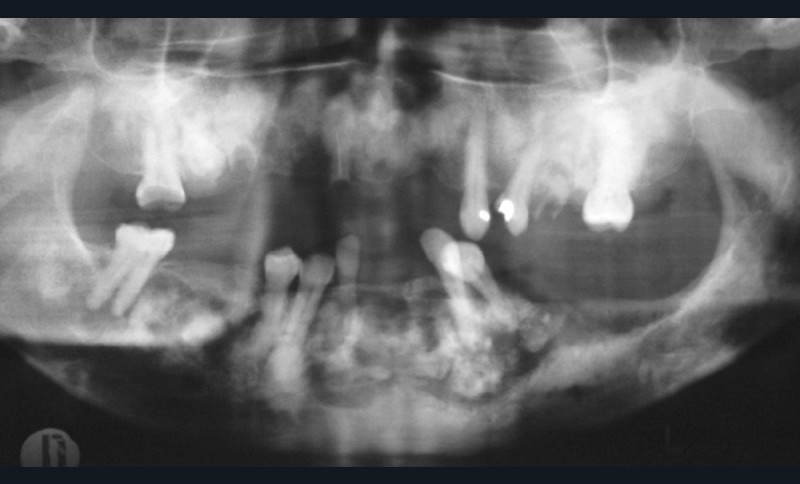

1. Dysplasie cémento-osseuse (DCO) de type floride au stade d’ostéomyélite.

• La dysplasie cémento-osseuse est une lésion fibro-osseuse rare de la mâchoire qui peut affecter certains secteurs (forme péri-apicale), ou les quatre cadrans (forme floride) (fig. 1). Au niveau radiologique, elle se caractérise dans cette dernière, par de multiples lésions osseuses denses et lobulées, souvent situées de manière symétrique dans plusieurs régions de la mâchoire (fig. 2). Ces lésions osseuses prédisposent au développement d’ostéomyélite maxillo-mandibulaire notamment en cas de geste invasif exposant l’os ou en cas d’infection dentaire. S’il est clairement contre-indiqué de recourir à la chirurgie implantaire dans les zones atteintes par la DCO, il pourrait en revanche être envisageable de poser des implants dans les zones indemnes [19,20].